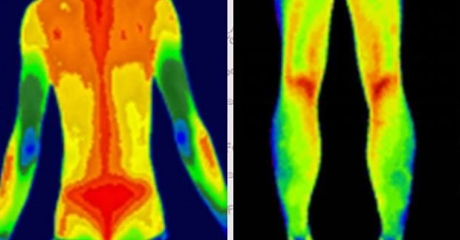

(插入示意圖:脊柱炎癥熱圖 – 紅色熱區與MRI病灶位置完全吻合)

血管病變預警

自動標注肢體溫差>1℃的區域(提示血栓風險)

動態監測糖尿病足微循環變化

案例:北京某三甲醫院用其提前7天預警糖尿病患者足部壞死風險